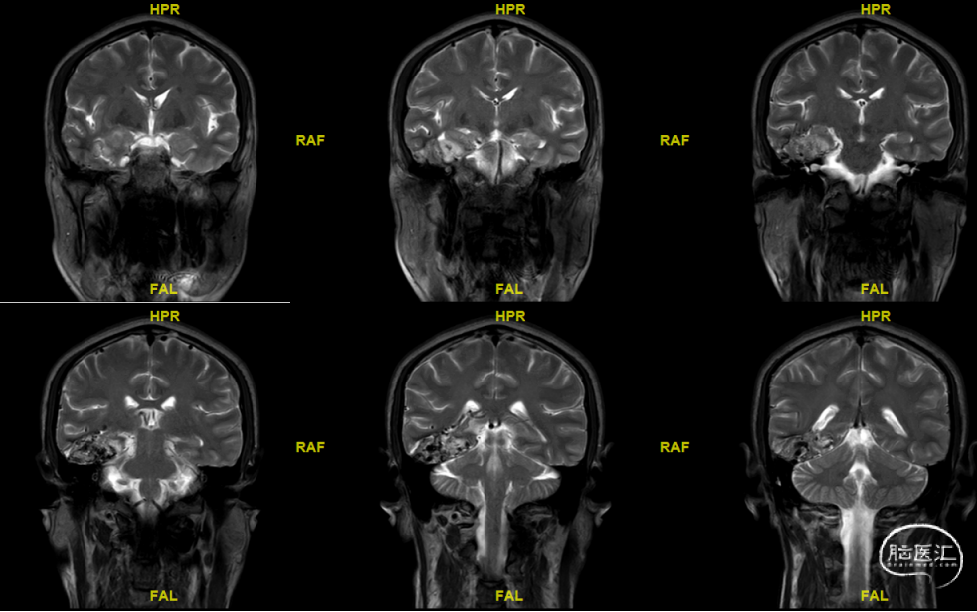

术前MRI

根据AVMs的位置分布,其引流静脉非常多变,可以引流到不同的浅静脉及深静脉系统。颞叶外侧面AVMs的引流静脉常常向下引流,然后汇入Labbe静脉,最后流向横窦。颞叶内侧面和底面的AVMs常常引流至直窦,罕见引流至蝶窦、岩窦或居中的基底静脉。颞叶浅静脉引流侧裂表层的AVMs。

理解AVM六面体结构